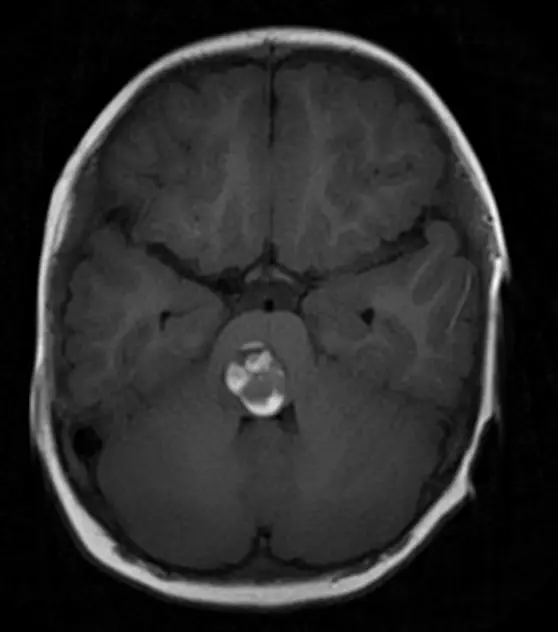

腦干腫瘤患者術后2年最新隨訪:“病灶全切,不必再擔憂!”

一次突發(fā)的左側肢體無力,讓37歲的中國香港患者佩珊被診斷出腦干橋腦海綿狀血管瘤出血,她的人生也陷入了手術可能會癱與再次出血可能致殘的兩難絕境。 就在這時,一場看似不可能的手術...

“我再也不用擔心出血了!”腦橋海綿狀血管瘤患者術后2年最新隨訪:病灶全切,不必再擔憂!

當巴教授回復的郵件上寫著COMPLETE cavernoma removal(病灶全切)的字樣映入眼簾,這些曾讓佩珊提心吊膽的日夜,如今終于可以畫上句號。 2023年7月,佩珊因左側肢體無力就醫(yī)后被診斷出腦干橋腦...